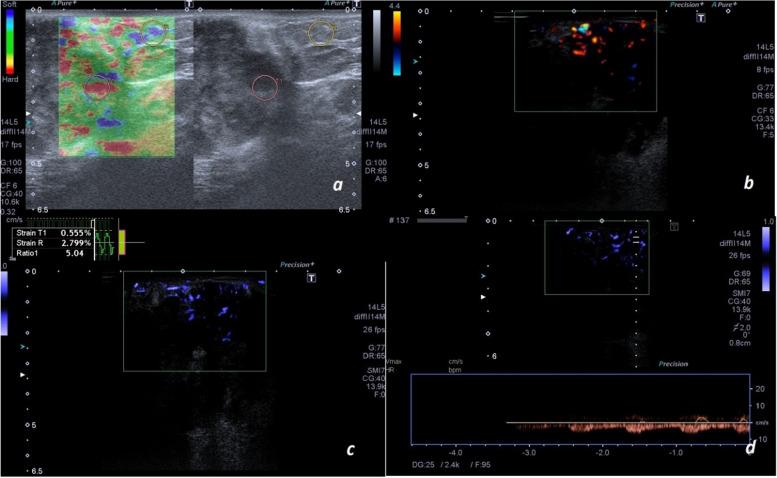

Breast ultrasound is highly sensitive, but its specificity is not as high for detecting malignant lesions. Auxiliary modalities like elastography, Color and Power Doppler ultrasound are used as adjuncts to yield both a high sensitivity and specificity. Superb microvascular imaging (SMI) is a newer modality with more accuracy for detecting breast lesions. In this study, our goal was to investigate the role of SMI as an adjunct to ultrasound and find a suitable combination model for the evaluation of breast masses.

METHODS

In this cross-sectional study, 132 women with 172 breast masses who underwent ultrasound-guided biopsy were included.. The ultrasound features of the lesion, the strain ratio in strain elastography, the number of vessels for each lesion, their morphology and distribution in Doppler and Power Doppler ultrasound and SMI were recorded for each lesion. A vascular score and a vascular ratio were defined.

RESULTS

In the histologic examination, 31 lesions (18%) were malignant and 141 lesions (82%) were benign. The vascular score was more accurate than the vascular ratio in all three modalities. The predictive ability of strain ratio was higher than Doppler and Power Doppler ultrasound and SMI. Adding SMI alone to ultrasound increased the specificity from 46.10% to 61.2% and the accuracy from 55.80% to 70.11%. In the combination of ultrasound with other modalities, the best was the combination of ultrasound, strain elastography, and SMI; which yielded a specificity and sensitivity of 100% and 74.4%, respectively.